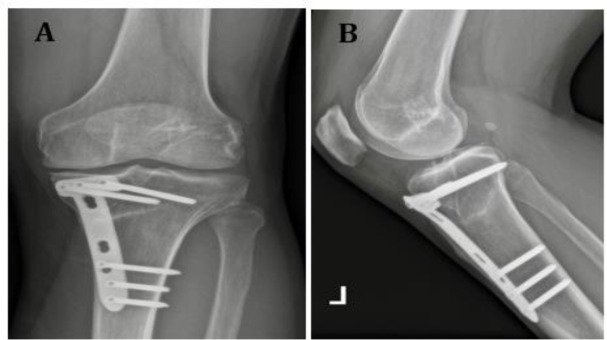

同时进行前交叉韧带(ACL)重建(ACLR)和外翻高胫骨截骨术(HTO)可减轻70%前交叉韧带缺损和股胫骨骨关节炎患者的疼痛,使膝关节在10年随访中保持稳定,33%-80%的病例可重返运动场(RTS),但39%的病例会出现股胫骨骨关节炎进展。并发症发生率为 0% 至 23.5%(6.5% 为翻修外翻 HTO,17.5% 为前交叉韧带移植失败,7.7% 为静脉血栓)。对于患有前交叉韧带缺损和股胫骨屈曲性骨关节炎并伴有胫骨后斜坡过高(PTS)的患者,同时进行前交叉韧带重建和HTO可获得令人满意的效果,而且似乎对重建后的前交叉韧带进一步断裂具有保护作用。患者年龄越小、运动需求越多,我们就越倾向于进行联合干预(前交叉韧带重建和外翻 HTO)。

Simultaneous anterior cruciate ligament (ACL) reconstruction (ACLR) and valgus high tibial osteotomy (HTO) alleviates pain in 70% of individuals with ACL deficiency and varus femorotibial osteoarthritis, allows for sustainable stabilization of the knee at the 10-year follow-up and a return to sport (RTS) in 33%-80% of cases, but femorotibial osteoarthritis progression occurs in 39% of cases. The complication rate ranges from 0% to 23.5% (6.5% revision valgus HTO, 17.5% ACL graft failure, 7.7% venous thrombosis). Simultaneous ACLR and HTO leads to satisfactory results in patients with ACL deficiency and varus femorotibial osteoarthritis associated with a high posterior tibial slope (PTS) and appears to have a protective effect on further ruptures in the reconstructed ACL. The younger the patient and the more sporting demands he/she poses, the more we should be inclined to perform a combined intervention (ACLR and valgus HTO).